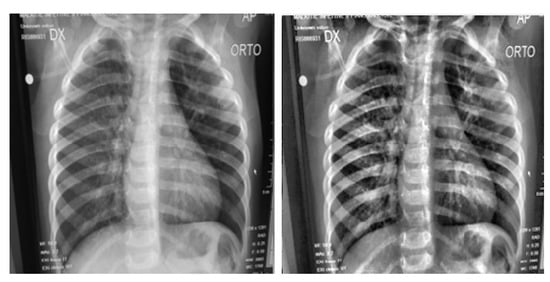

3.1. Preprocessing